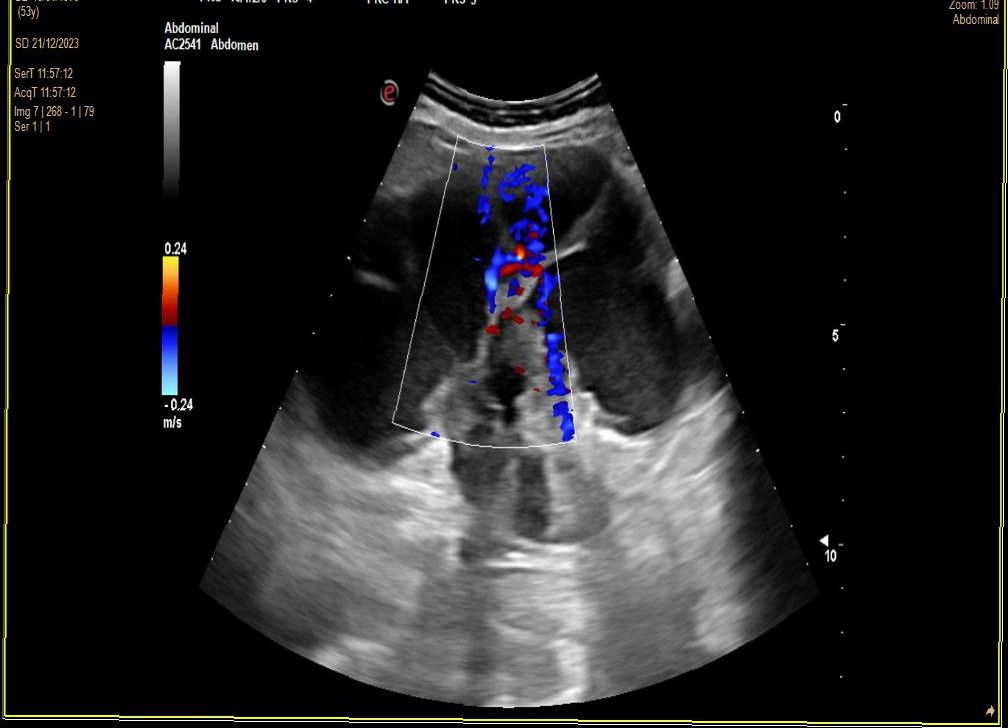

Derivación UHR (contacto telefónico). Ecografía Rx hospital. RD: Ecoestructura heterogénea. Diferenciación corticomedular alterada. Alteración morfológica. Dilatación hidronefrosi grau IV. No aumento de vascularización. RI: No se observan alteraciones.

TC 15 días. Enfisema paraseptal y centrilobulillar. Renal derecha neoformación hiperdensa en pelvis y uréter con coágulos, atrofia parenquimatosa, dilatación urétero-pielo-calicial sin litiasis. Hígado cúpula con calcificación periférica, valorar quiste hidatídico.